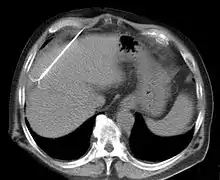

RFA may be performed to treat tumors in the lung,[6][7][8] liver,[9] kidney, and bone, as well as other body organs less commonly. Once the diagnosis of tumor is confirmed, a needle-like RFA probe is placed inside the tumor. The radiofrequency waves passing through the probe increase the temperature within tumor tissue and results in destruction of the tumor. RFA can be used with small tumors, whether these arose within the organ (primary tumors) or spread to the organ (metastases). The suitability of RFA for a particular tumor depends on multiple factors.